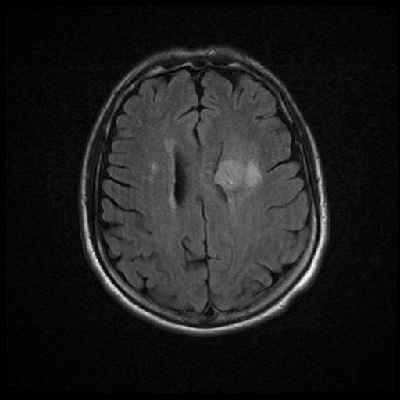

Neurologic and mental examination showed intact immediate memory but inability to recall 3 objects in 5 minutes. He was not oriented to time or space or situation but oriented to person. His remote memory was intact. There was left superior quadrantonopsia but no focal motor or sensory deficits. FLAIR images on MRI showed a lesion in the left mesial temporal lobe (Panel 1). This lesion had increased T2 signal but without enhancement on T1 images. This lesion also had mass-effect and edema within that region. On FLAIR images, there were some small foci of abnormal signal in the white matter of the right parietal lobe (Panel 2) but these foci did not enhance (Panel 3). There is a vague, poorly demarcated, triangular shaped periventricular signal abnormality in the left parietal lobe (Panel 2) but this area did not enhance (Panel 3). On another image (obtained higher to Panel 2 and 3), however, there is a small cluster of enhancing spotty signal in the white matter of the left parietal lobe (Panel 4) and the largest focus is about 0.4 cm in diameter. There were areas with features of encephalomalacia in his right mesial temporal lobe that would be explained by his history of prior infarct.

2. FLAIR |